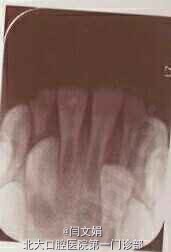

11见开髓孔,唇侧穿通,髓腔内见封药棉捻,x线示牙根形成约三分之一

11牙髓血运重建,术后三个月牙根继续发育,形态以及发育程度与对侧同名牙基本相同